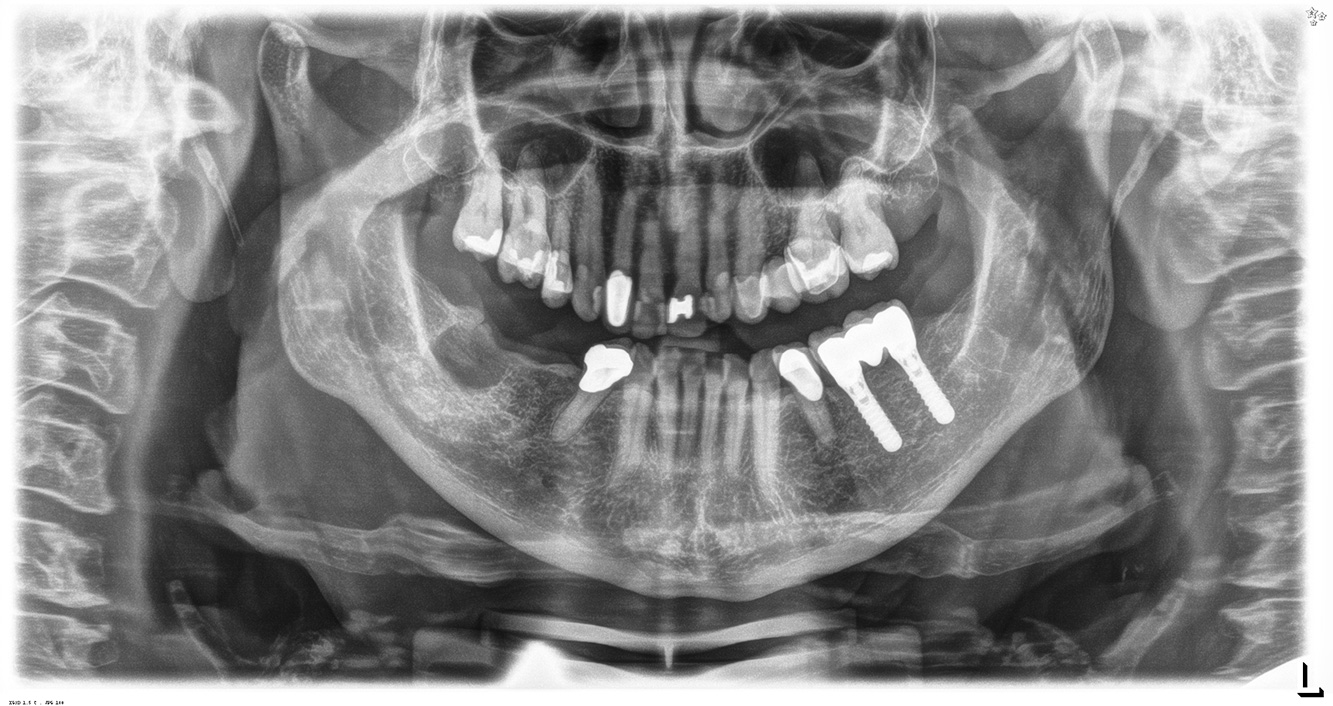

The 68-year-old patient has no general health conditions and is not taking any medication that may be relevant to her oral health, and her lifestyle does not pose any particular risk. The patient has two dental implants (3rd quadrant, for five years) and a previous case of periodontal disease (stage IV, grade B periodontitis) with tooth loss. Currently the periodontal conditions are stable. However, periodontitis significantly increases the biological complications of implantations and there is a risk of implant loss (21). Four recommendations can be determined for the prophylaxis session.

As the patient does not have any particular risk factors with specific dental implications, the requirements determined from her current state of oral health are crucial. Here, it is recommended that a thorough assessment of periodontal condition be carried out once a year. This will ensure that any potential progression of the previous periodontal disease or development of peri-implantitis can be responded to in good time.

Because the patient has implants and a history of periodontal disease, she is at risk of developing peri-implantitis. It is therefore recommended that she attend a recall session every three to four months.